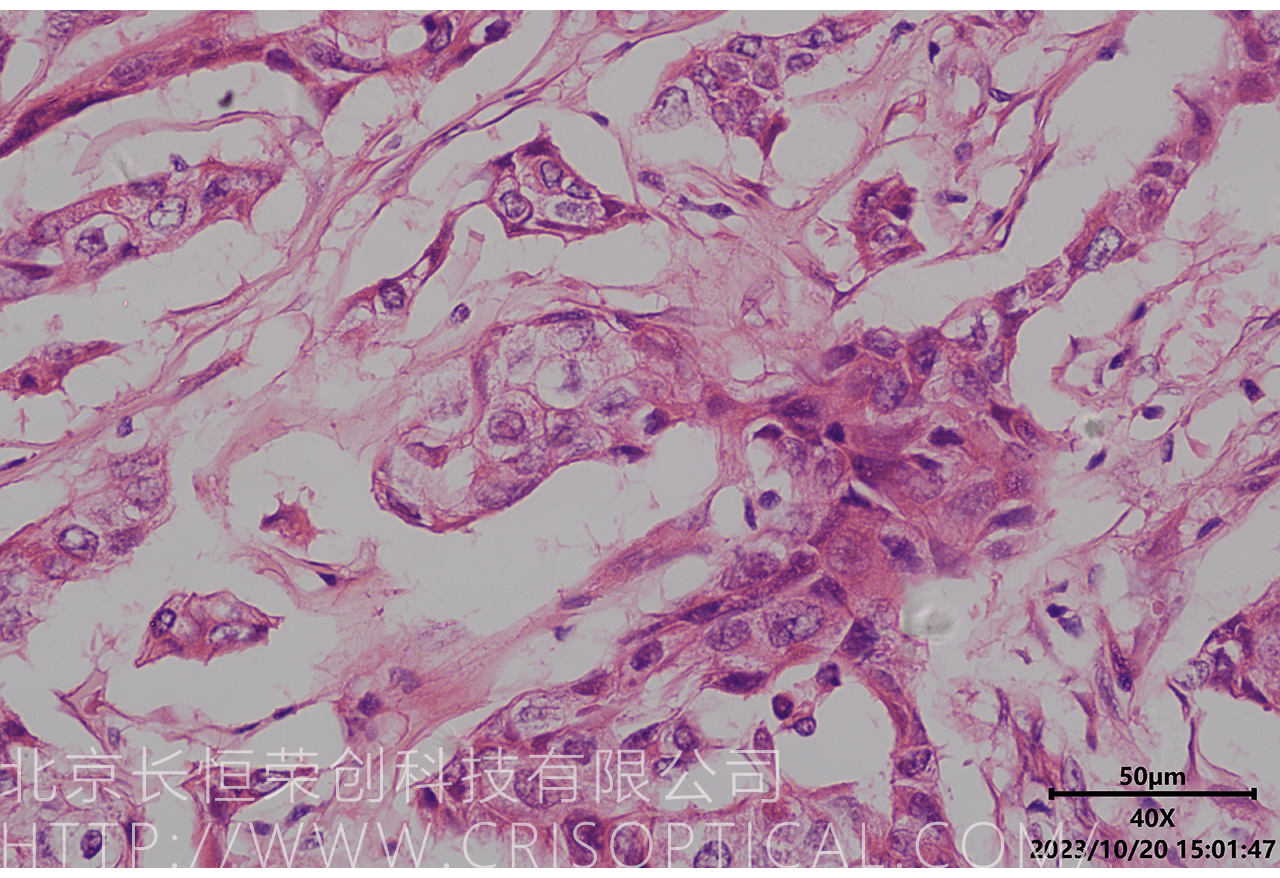

腫瘤診斷:對(duì)癌癥和其他腫瘤的病理切片觀察是確定腫瘤類型、分級(jí)和分期的關(guān)鍵步驟。醫(yī)生通過(guò)觀察組織樣本中的細(xì)胞形態(tài)、核形狀、分裂活性和其他特征,可以識(shí)別腫瘤的類型,幫助決定治療方法。